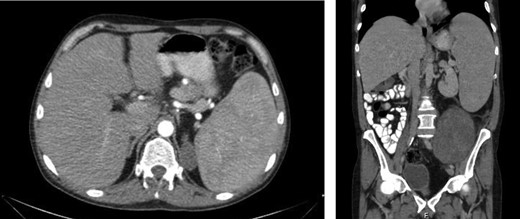

Laboratory work-up revealed a white blood cell count (WBC) of 1.0 K/ul, an absolute neutrophil count of 680, and an absolute lymphocyte count of 310. He was anemic with a hemoglobin of 6.9 g/dl. Rheumatoid factor was elevated to 180 IU/ml. An antinuclear antibody screen was positive at 1:320. Computed tomography (CT) of the abdomen and pelvis showed an enlarged spleen and a large heterogeneous mass in the left abdomen extending into the pelvis (Figs 1 and 2). A bone marrow biopsy showed abnormal CD3+ and CD8+ T-cell lymphocytosis with TCR(beta)+ and CD57+, consistent with the diagnosis of T-cell large granular lymphocytic leukemia.

Axial and coronal CT images demonstrates the large retroperitoneal mass (50 × 33 × 16 cm) displacing bowel, the left kidney, left iliac vessels and bladder to the right.